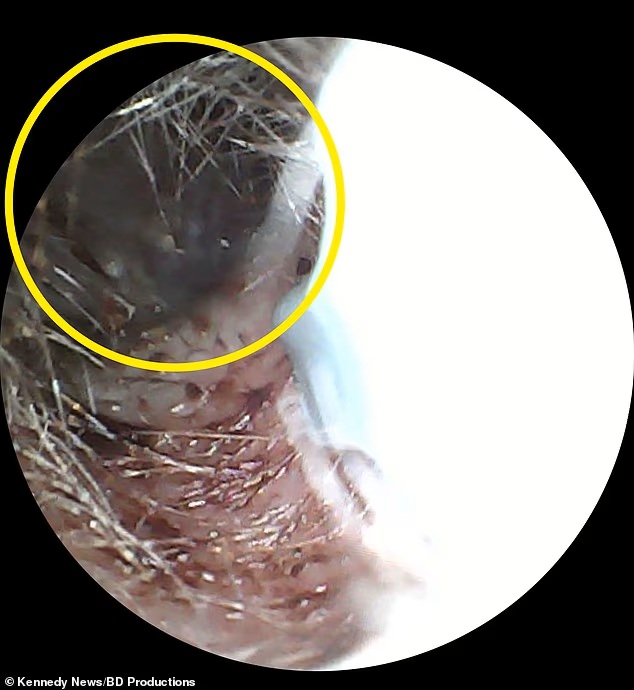

Μόνο όταν μια νοσηλεύτρια εξέτασε προσεκτικά το αυτί του εργάτη εργοστασίου, αποκαλύφθηκε η αλήθεια: ένα μαύρο σκαθάρι μήκους περίπου πέντε εκατοστών είχε εισχωρήσει βαθιά στο αυτί του και κινούνταν. Το έντομο δεν είχε απλώς εισχωρήσει — φαινόταν να έχει «φωλιάσει» στο εσωτερικό του αυτιού, προκαλώντας του αφόρητο πόνο.

«Ήταν φρικτό», δήλωσε ο ίδιος. «Κάθε ήχος που έκανε ήταν πολλαπλάσιος εξαιτίας της εγγύτητάς του με το αυτί, και είχε δαγκάνες, οπότε με τσιμπούσε ξανά και ξανά».

Η απομάκρυνση του εντόμου έγινε με αλοιφή και βαμβάκι, αφού πρώτα οι νοσηλεύτριες το είχαν εξουδετερώσει.